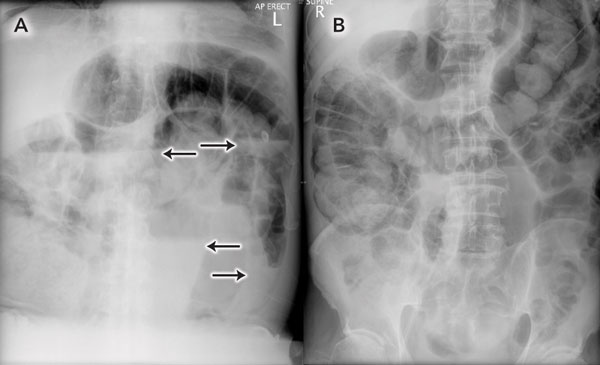

Renal tract ultrasound showed no obstructing lesion, with normal kidney size and morphology. Plain imaging (Box 2) and computed tomography (CT) of the abdomen and pelvis with intravenous and oral contrast demonstrated distension of the small bowel up to 4 cm in diameter, with a caecal diameter of 10 cm. Fluid material filled the sigmoid colon and rectum. A non-obstructing, exophytic mass arising from the lateral wall of the rectum, measuring 5 × 9 × 7 cm, was noted. A presumptive diagnosis of colonic pseudo-obstruction due to fluid and electrolyte imbalance was made.

2 Erect (A) and supine (B) abdominal x-rays taken on admission

Note the uniform dilation of the large bowel, with multiple air–fluid levels (arrows). |